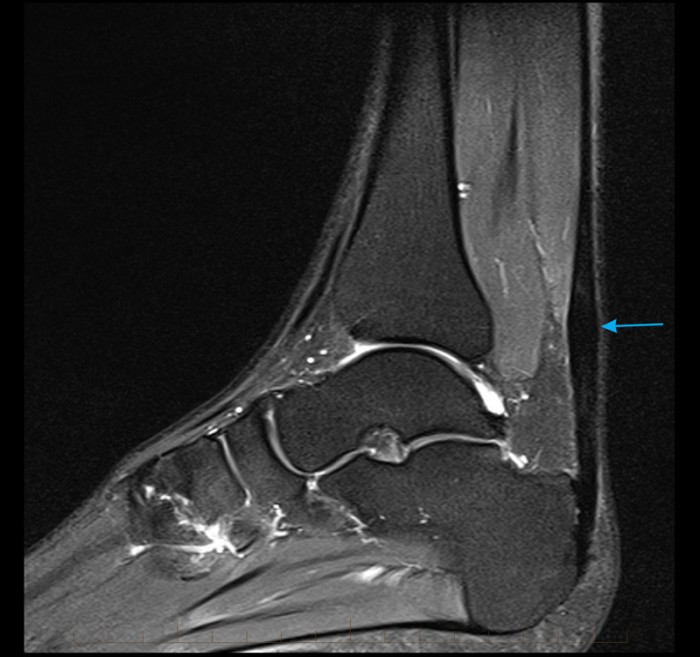

From www.mri.melbourne

MRI Achilles Tendon Melbourne Radiology Soleus Tendinopathy — differentiating strains of the gastrocnemius or soleus is important for treatment and prognosis. — in this article, learn about the different grades of soleus strain and how a person can treat them with gentle stretches and first aid. the presentation of a soleus strain tends to be far less dramatic than that seen in the gastroc. Soleus Tendinopathy.

MRI Achilles Tendon Melbourne Radiology Soleus Tendinopathy — learn how to strengthen your soleus muscles, and why soleus strength is important in runners who suffer from calf and achilles tendon injuries. — soleus muscle injuries can be acute or chronic and are usually considered to be a minor discomfort by both the. the presentation of a soleus strain tends to be far less dramatic. Soleus Tendinopathy.